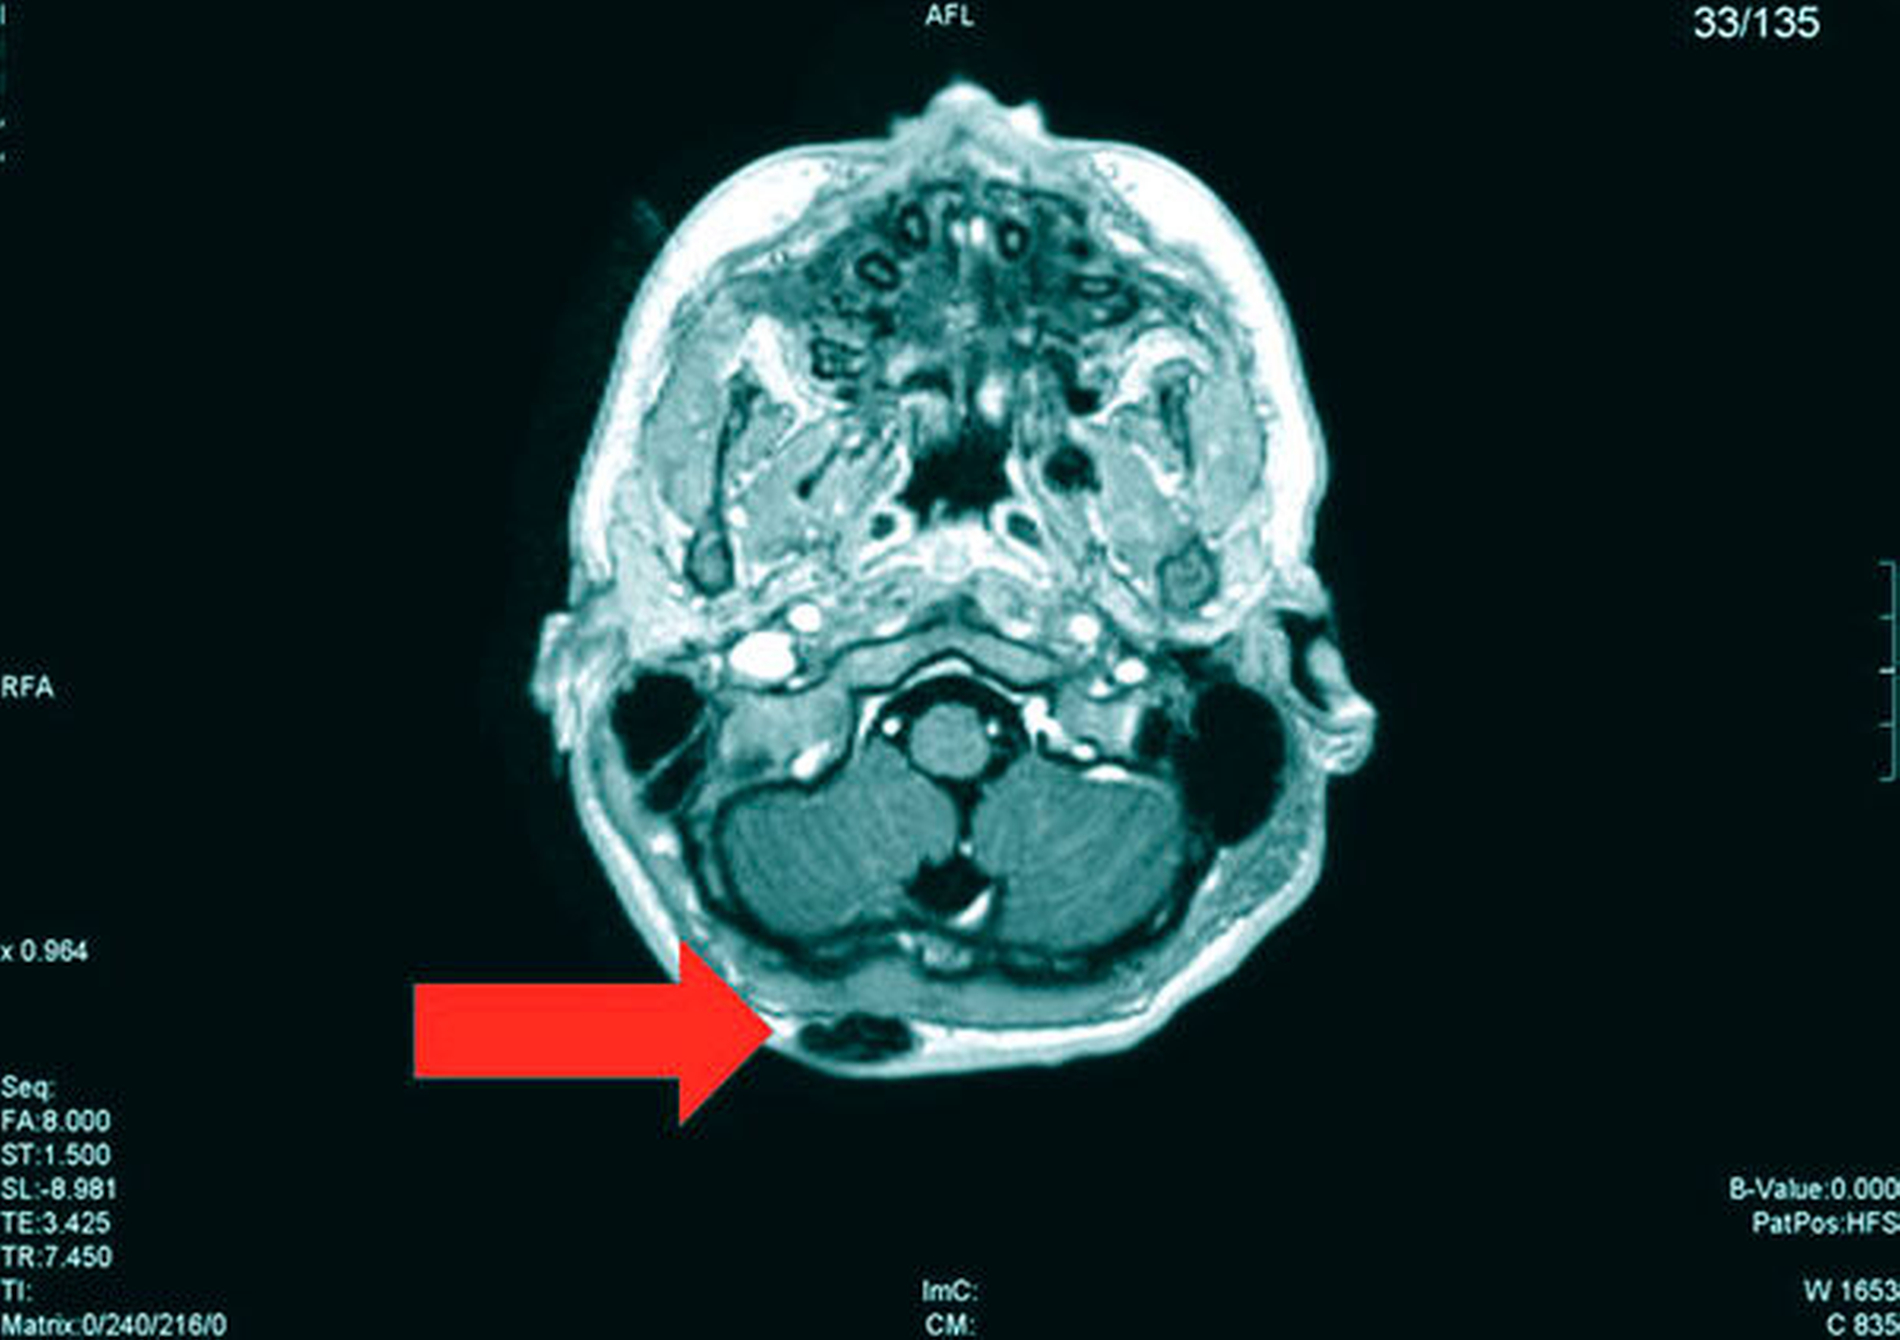

Die Magnetresonanztomografie des Neuro- und des Viszerokraniums erbrachte den Nachweis eines Areals erhöhter Kontrastmittelaufnahme im Bereich des basalen Kieferwinkelrandes links mit einer Ausdehnung von 3,1 cm x 2,3 cm. Im Bereich der behaarten Kopfhaut zeigten sich subkutan T1-hypointense, zum Teil polylobulierte Läsionen mit Verdacht auf epidermale Zysten sowie subgaleale T2-hypointense, flächig kontrastmittelaufnehmende Läsionen mit Verdacht auf Osteome (Abbildungen 3a bis 3d).